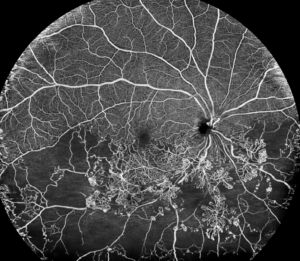

O diagnóstico é feito através do mapeamento de retina (fundo de olho) e confirmado com tomografia da retina (OCT).

Esta tecnologia revolucionária permite um diagnóstico mais detalhado e não invasivo das condições que afetam a retina e a circulação ocular. Na Clínica Roisman, oferecemos